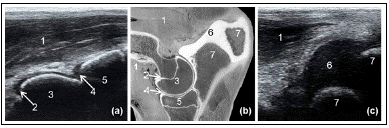

Ultrassonografia longitudinal cranial (letra a) e caudal (letra c) do cotovelo (letra b) de um bezerro. Quais são as estruturas identificadas de 1 a 7 no exame ultrassonográfico a partir do corte anatômico do cotovelo?